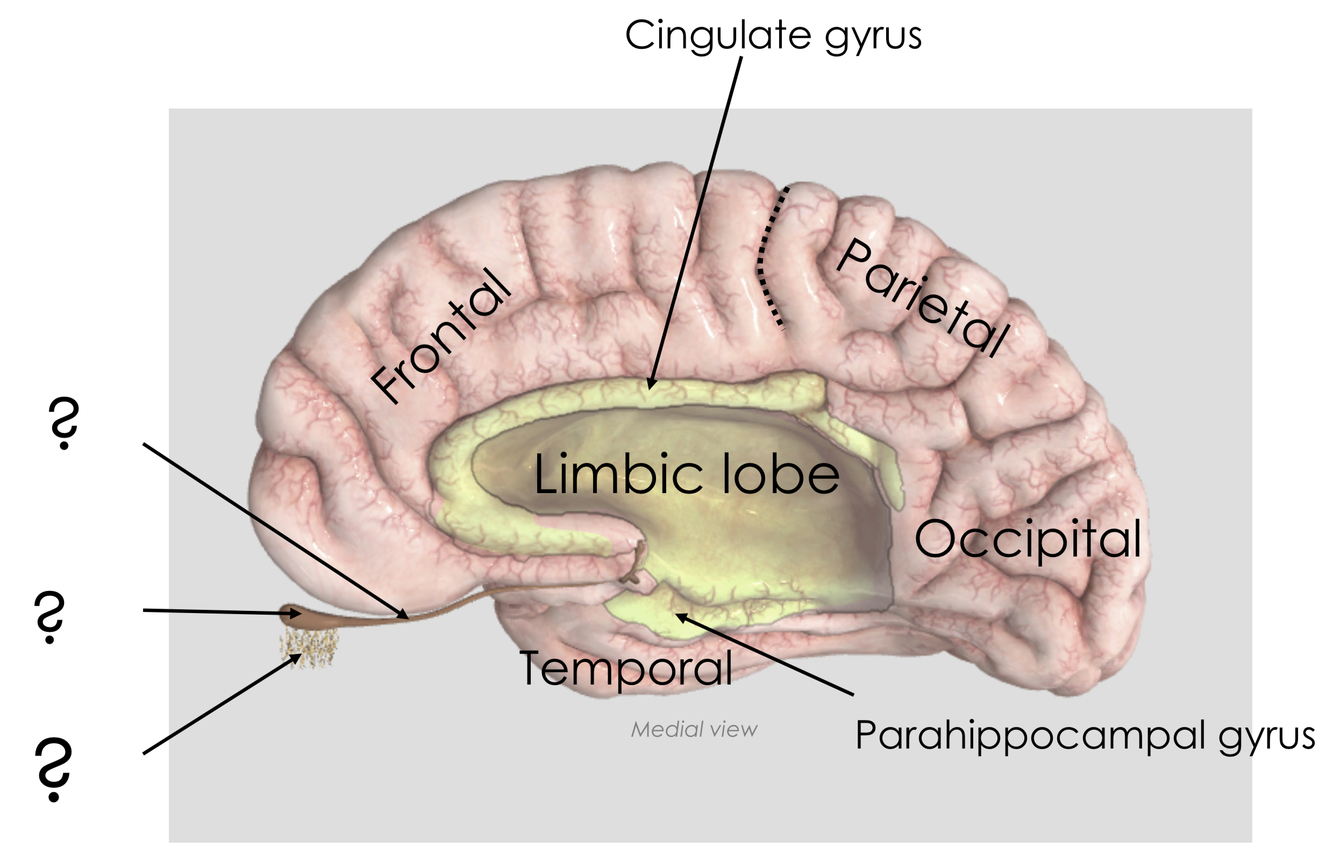

What are the following structures?

What is significant about their relationship with the limbic system?

The olfactory tract is involved with the limbic system

smell can trigger emotions, memories and autonomic nervous system responses

the olfactory bulb and olfactory tract are outgrowths of the telencephalon - olfaction is the only sensory system to bypass the thalamus on the way to the cerebral cortex